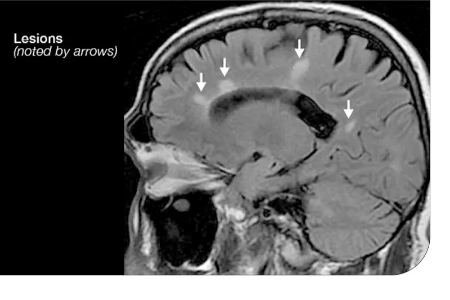

-- MRI مغز و نخاع

MRI دقیق ترین ابزار تشخیص ام اسه.

در این تست، پزشک نقاط سفید کوچکی رو می بینه (پلاک ها) که نشون دهنده ی آسیب میلین هستن. MRI با تزریق دقت بیشتری داره و ضایعات فعال رو هم نشون می ده.